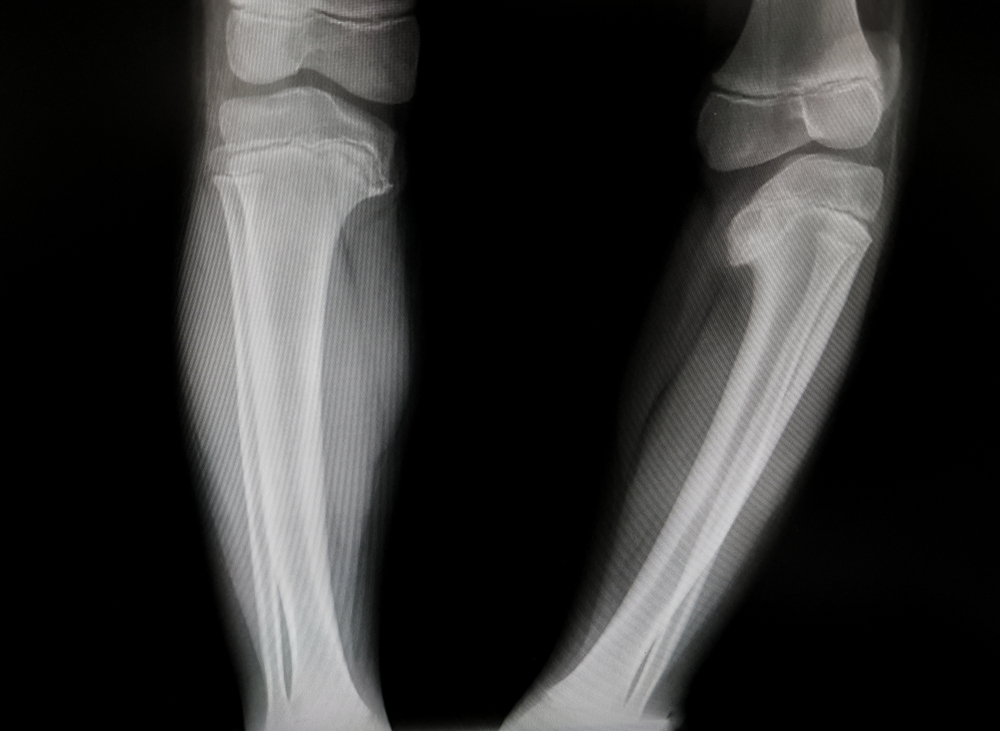

Torsión de Tibias

Esta afección se refiere a la torsión hacia adentro de los huesos que están entre la rodilla y el tobillo. Hace que los pies del niño apunten hacia adentro. Se percibe comúnmente en niños que empiezan a caminar. Puede ser ocasionada por la posición del bebé en el útero.

La torsión tibial suele mejorar con el tiempo. A medida que el niño crece, la marcha se hará más normal, por lo general, alrededor de los 5 y 8 años de edad.